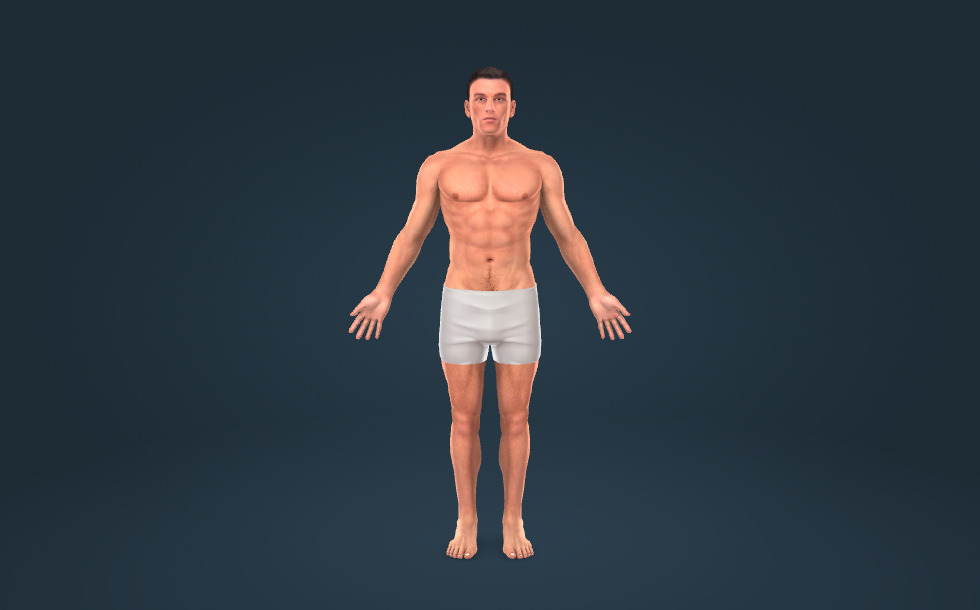

Hình ảnh này giới thiệu về các hệ cơ quan quan trọng nhất của cơ thể người.

Cơ thể nam giới

Cơ thể nam giới